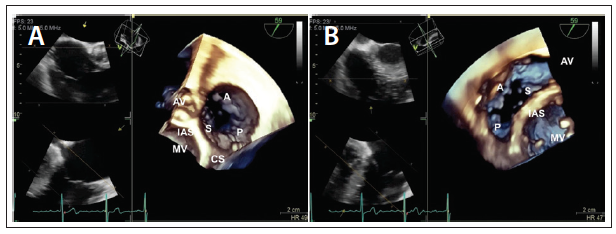

Three-dimensional imaging has significantly enhanced our understanding of the tricuspid valve anatomy and enabled accurate identification of the tricuspid valve leaflets and the surrounding structures. Standardization of the tricuspid valve 3D image display has been recommended by the ASE to facilitate communication between the echocardiographer and the interventional cardiologist.27 Regardless of whether the 3D image of the tricuspid valve is displayed from the RV or the RA side, the interatrial septum and the adjacent mitral valve are placed at 6 o’clock. When the tricuspid valve is viewed from the RA side, the aortic valve is placed to the left side (Figure 5A); however, when the tricuspid valve is viewed from the RV side, the aortic valve is placed to the right (Figure 5B).